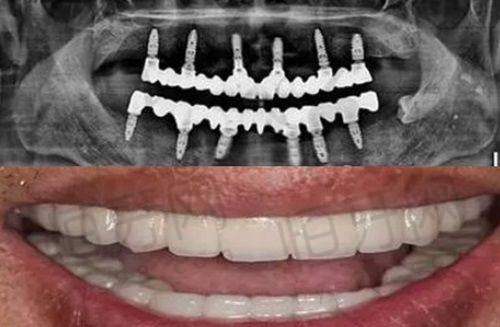

种植牙项目:种植牙是衢州开化可恩口腔门诊部的特色项目之一。随着人们生活水平的提高,对牙齿缺失修复的要求也越来越高。种植牙作为一种精良的牙齿修复方式,具有美观、舒适、耐用等优点。门诊部采用了精良的数字化种植技术,能够精细地确定种植位置和角度,提高种植的成功几率。医生们会根据患者的口腔情况和身体状况,为患者选择合适的种植体,确保种植成效自然美观,与真牙无异。

口腔CT设备:口腔CT能够清晰地显示口腔内部的结构,包括牙齿、牙槽骨、神经等。通过口腔CT,医生可以更正确地了解患者的口腔状况,为种植牙、正畸等手术提供详细的三维图像,从而制定更加精细的治疗方案。与传统的X光片相比,口腔CT的图像更加清晰、正确,能够大大提高手术的成功几率。

评价二:“我因为牙齿缺失,想做种植牙手术。在朋友的推荐下,我来到了衢州开化可恩口腔门诊部。医生在手术前给我做了详细的检查和评估,制定了个性化的种植方案。手术过程中,医生操作非常熟练,而且有精良的设备支持,整个手术特别顺利。术后,医生还定期回访我,关心我的修复情况,让我感觉特别贴心。现在我的种植牙已经修复得良好了,吃东西也特别方便。”